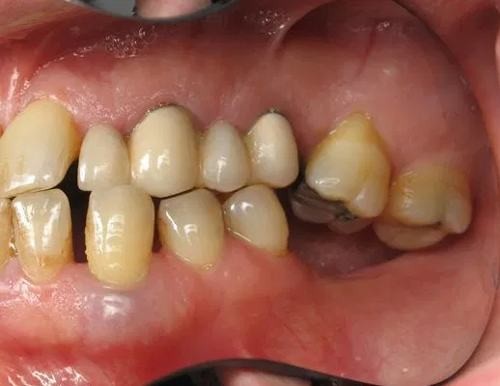

2.2. Xô lệch răng và sai lệch khớp cắn

Việc mất răng dẫn đến tình trạng các răng kế cận bị dịch chuyển và gây ra rối loạn khớp cắn. Các răng trên cung hàm vốn tạo thành một khối thống nhất, hỗ trợ lẫn nhau và phân bổ đều lực nhai. Khi một răng mất đi, răng ở hàm đối diện không còn điểm tựa, sẽ dần di chuyển trồi lên hoặc lún xuống để tìm điểm tiếp xúc, từ đó phá vỡ khớp cắn tự nhiên. Điều này ảnh hưởng đến hoạt động nhai cắn, gây đau nhức khi nhai và tác động lâu dài đến chức năng của hàm.

Mất răng cũng làm cho lực nhai không được phân bổ đồng đều. Hai răng bên cạnh khoảng trống sẽ mất đi điểm tựa và có khuynh hướng nghiêng hoặc di chuyển về phía đó. Lâu ngày, điều này tạo ra các khoảng trống mới, khiến các răng khác tiếp tục dịch chuyển, gây ra tình trạng chen chúc, sai lệch khớp cắn và ảnh hưởng đến thẩm mỹ. Đặc biệt, khi mất răng hàm, nguy cơ lệch khớp cắn sẽ nặng hơn, có thể dẫn đến liệt cơ hàm và lệch mặt.

Bên cạnh đó, các kẽ răng mới hình thành do sự xô lệch cũng khiến thức ăn dễ bị mắc kẹt, tạo điều kiện cho vi khuẩn sinh sôi, làm tăng nguy cơ mắc các bệnh lý răng miệng khác.